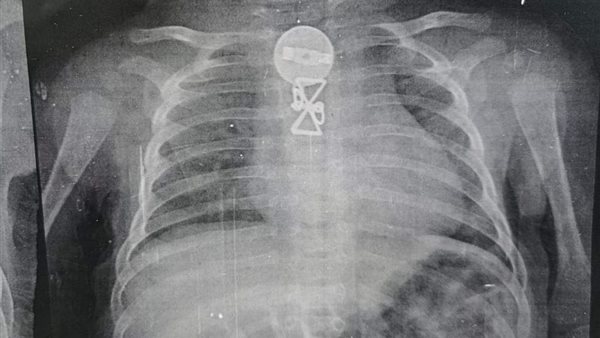

وأشار رئيس الفريق الطبي، أن المستشفى استقبلت الطفل وكان يعانى من التنفس وتم حجزه بالمستشفى وعمل الإشاعات اللازمة وتبين وجود جسم معدني داخل الجسد وتم استخراجه ، وتم العرض على والديه الذين أقروا ان شقيقته الكبرى كانت تداعبه و قام ببلع تلك الجسم المعدنى منذ فترة.